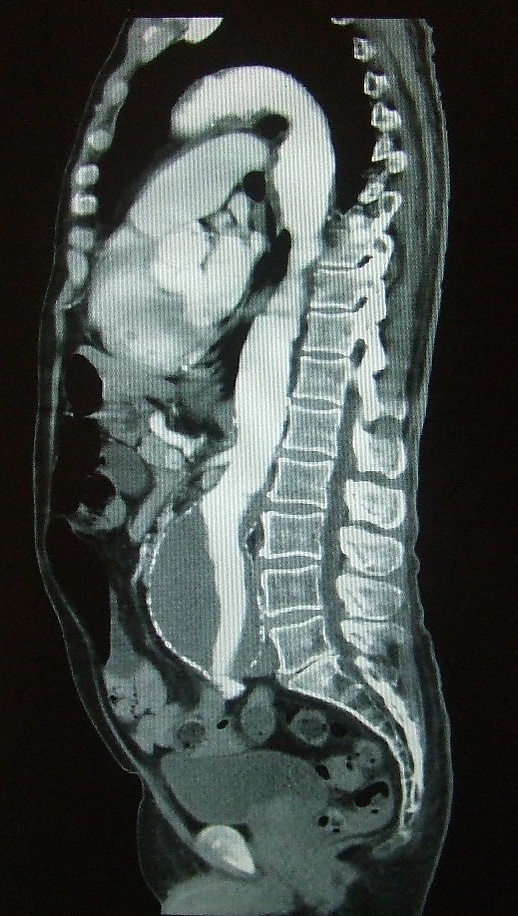

Болюсное контрастное усиление — один из наиболее распространённых методов контрастного усиления в компьютерной томографии, посредством внутривенного введения автоматическим инъектором контрастного препарата со скоростью от 2 до 7 мл в секунду. С этой целью применяют, как правило, неионные йодсодержащие препараты из расчета 2 мл на 1 кг массы обследуемого. Данный метод позволяет оценивать структуру сосудов (КТ-ангиография), выявлять и оценивать поражение паренхиматозных органов и др.

Болюсное контрастное усиление осуществляется для оценки сосудов (КТ-ангиография), для улучшения дифференцировки сосудов от лимфатических узлов, обнаружения и характеристики поражения паренхиматозных органов, оценки чашечно-лоханочной системы почек и мочевых путей, выявления воспалительного или опухолевого интерстициального усиления, анализа перфузии тканей.

Болюсное контрастное усиление представляет собой механически управляемую инъекцию контрастного препарата посредством мощного шприца-инъектора с установленной скоростью введения (в большинстве случаев неизменной в ходе исследования). Такой характер введения контрастного препарата позволяет получить оптимальные для различных целей фазы контрастирования.

Фазы контрастирования непосредственно связаны со анатомией и физиологией кругов кровообращения и кровоснабжением органов (см. Круги кровообращения человека). Время задержки после начала введения контрастного препарата перед началом КТ-сканирования выбирается с учётом органа, представляющего собой цель изучения. Большинство органов имеют артериальное кровоснабжение. Исключение представляют собой печень и лёгкие (печень кровоснабжается не только из системы воротной вены — 75-90 %, но и из печёночной артерии; лёгкие получают венозную и артериальную кровь из малого и большого кругов кровообращения, соответственно). Органы, имеющие преимущественно артериальную перфузию, наиболее хорошо накапливают контрастный препарат через 5-15 секунд после пика контрастного усиления аорты. Печень предпочтительно сканировать в портальную фазу, в которую отмечается контрастирование органа и из системы печёночной артерии, и из системы воротной (портальной) вены. Для улучшения качества диагностики сканирование в портальную фазу контрастирования лучше предварить сканированием в артериальную фазу.